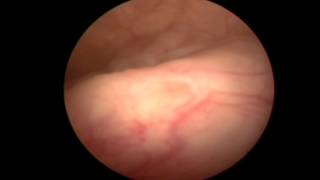

Μέθοδο TURis

Video Gallery